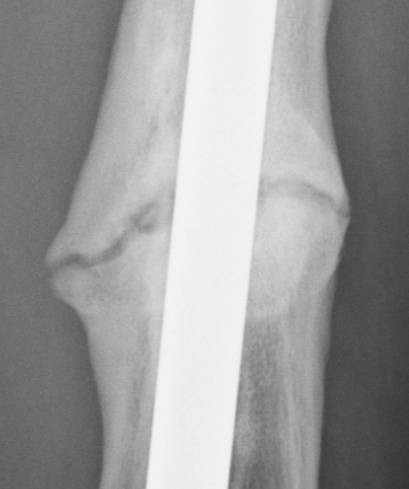

June 22, 2010 X-ray update

Forive me people for I have sinned. It has been two years since my last update. But seriously, there is much improvement to report. Based on activity and how it feels things are progressing very well. The x-rays also show more bone growth which adds to the good sign.

Feb. 21, 2008 jUNE 22, 2010